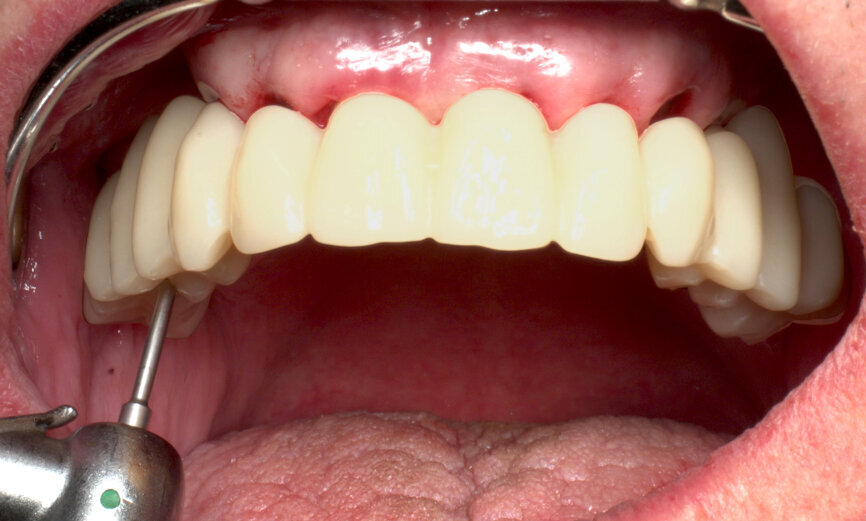

Returning to the patient, the healing caps were removed (Fig. 19), and the prosthesis was placed, allowing for a passive fit on the abutments, with an initial handpiece tightening of each SRA screw to 5 N cm. After the seating was checked, the torque of each SRA screw was increased, also with the handpiece, to 35 N cm (Fig. 20). The occlusion was checked and contacts were inspected (Fig. 21). The screw holes were sealed with PTFE and a temporary filling material. A panoramic X-ray was taken, and SRA screw positions were evaluated to confirm the perfect temporary bridge fit (Fig. 22). The patient was discharged on 500 mg of amoxicillin every 8 hours and 25 mg of dexketoprofen every 12 hours for one week. Oral hygiene and diet instructions were given, and a one-week follow-up appointment was scheduled.